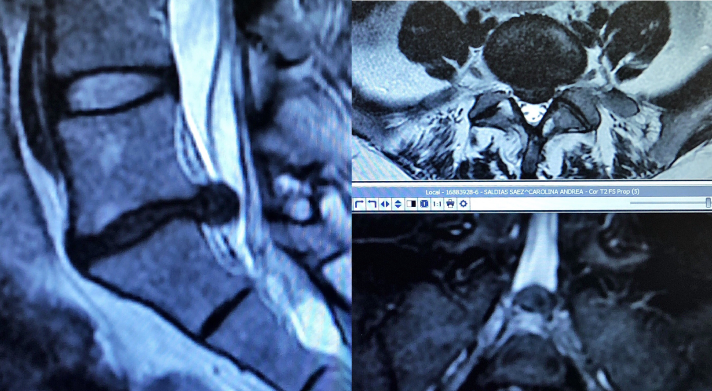

Resonancia Magnética de Hernia